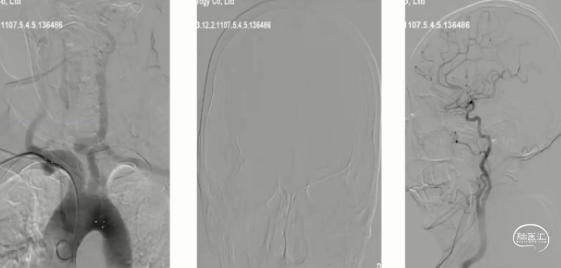

脑血管造影(主动脉弓及左侧颈内动脉2023-06-19):l型弓,左侧颈内动脉未见异常,前交通开放,右侧大脑前通过软脑膜支部分代偿

脑血管造影(双侧椎动脉正侧位):右侧大脑后通过软脑膜支部分代偿

脑血管造影 (右侧颈内动脉正侧位)